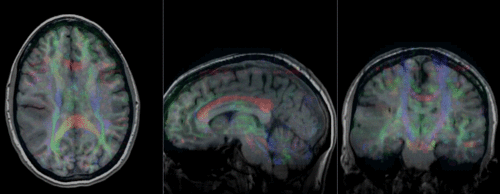

[[Image:RegLib_C29_registered.gif|500px|Registered DTI superimposed on SPGR and T2]] registered (cycles show T1 and T2 and color DTI overlay)<br>

Registered DTI superimposed on SPGR and T2 registered (cycles show T1 and T2 and color DTI overlay)